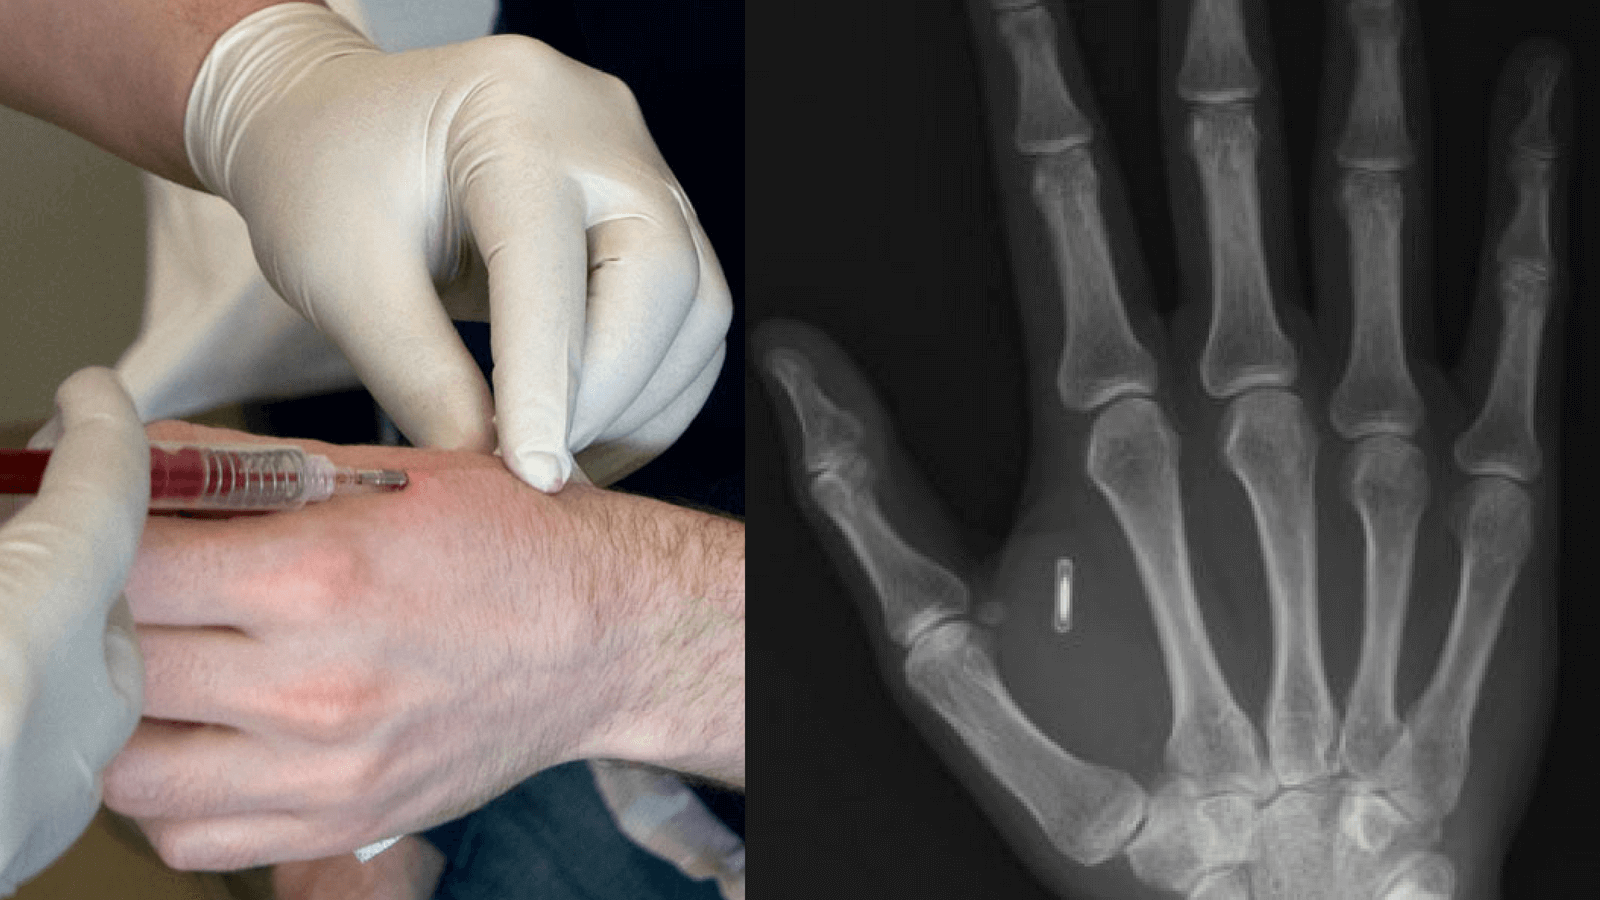

RFID cannot fit in an hyperdermic. It's like trying to pass a golf ball out of your cock.

RFID injection syringe looks like this (cdn.medicalfuturist.com) and has a diameter of 1.4mm.

Here is a veterinary injection syringe (files.hundeschule-a1.com) for micro-chipping. Look at the size of the hole.

RFID are measures at 14 gauge. They make hypodermics down to a 10 gauge. https://www.hamiltoncompany.com/laboratory-products/needles-knowledge/needle-gauge-chart Update. If you get an injection with a 14 gauge implant it will leave one big ass hole and would be similar to a core sample over a shot. This is some fake shit unless I see the hole it left coming out. The RFID chip shown in the pic is for large dogs. So she has that going for her.

14gauge needle still looks like a hole punch. (i.pinimg.com)

Like you said it would "leave one big ass hole". RFID that small would be ludicrously expensive to the point of being ridiculous even thinking you can chip the population. Also, you would feel a massive bump under the arm not to mention the transmitter on the RFID would be next useless that small for any receiver to pickup. So if the government were tracking you like the tinfoil hats are thinking, they would have to get to mm of the injection site to get a response.

The point is there is no, nor will there be RFID tracking chips in vaccines. Tracking chips also don't magically pick you up from satellite either, when your dog escapes they have to read their nape from less than 10cm away and that's with a big chip with a big antenna. Smaller chips cost more money and it defeats the purpose if a small chip has a huge antenna on it.